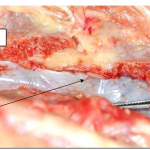

Photo INSERTIONS DE LA DURE-MERE SUR LE RACHIS Une anatomie redécouverte 28